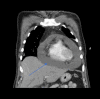

Abstract: Pembrolizumab is an immune checkpoint inhibitor used in various types of cancers. Pericardial tamponade is a rare side effect reported in only very few case reports. Early recognition and therapeutic intervention is vital in all cases. We report a case of a 54-year-old male with Stage 3 lung adenocarcinoma who developed cardiac tamponade secondary to pembrolizumab and subsequently required pericardial window.